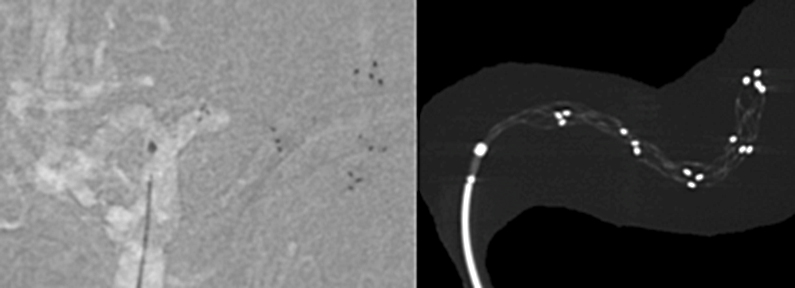

基本的に全身麻酔で治療を行います。足の付け根や肘にある太い動脈にカテーテルを入れて、レントゲンで確認しながら首や脳の詰まっている血管に移動させ、治療を行います。原則的には脳梗塞を起こしてから8時間以内の患者さんに行うことができますが、前に説明したように脳梗塞の範囲や側副血行の程度によっては24時間以内であれば行うことがあります。

ステントは心筋梗塞や狭心症の時に細くなった心臓の血管を広げる時に使われているものとして知られております。ただ、血栓回収療法の時は少し違った使い方をします。血栓で詰まったところでステントを広げると、ステントが広がり血栓を押しつぶします。すると一時的に脳の血流が再開します。ただ、このまま様子をみるとステントの金網の中に血栓がめり込みます。そのうちめり込んだ血栓により再度血管が詰まってしまいます。これでは意味が無いのでは、と思ってしまいますが、再度詰まることでステントが血栓に絡んだと判断できます。そうすれば、このステントをゆっくり引くとステントに絡んだ血栓も一緒に引けて来て、ステントを抜去すると血栓も取り除くことができます。うまくいけば、1回で詰まった血栓を除去できます。